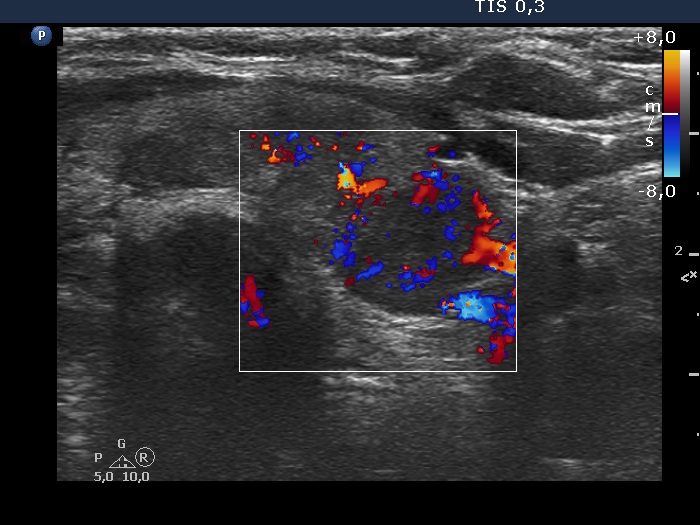

Discrete lesion or nodule in Hashimoto's thyroiditis - case 36 (691) (ultrasonographic picture 7)

Lower part of the left lobe, transverse scan, color Doppler mode. The lesion has intralesional vascularity.